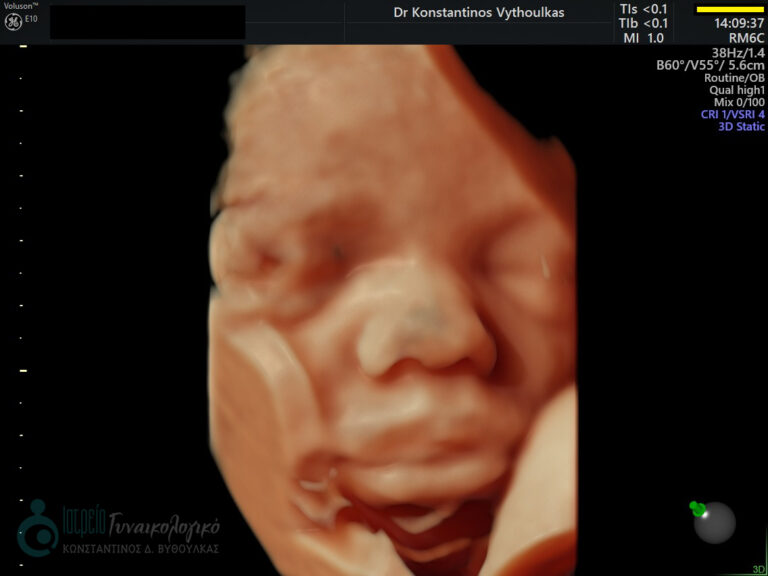

- Υπερηχογραφική εξέταση, η οποία συμβάλλει στη διαπίστωση της ενδομήτριας κύησης και αποκλεισμό της έκτοπης κύησης. Επιπλέον, μπορεί να διαπιστώσει εάν πρόκειται για μονήρη ή πολύδυμη κύηση, να ανιχνεύσει την εμβρυϊκή καρδιακή λειτουργία μετά τις 6 εβδομάδες και να προσδιορίσει υπερηχογραφικά την ηλικία κύησης, με βάση το κεφαλουραίο μήκος του εμβρύου μετά τις 8 εβδομάδες.